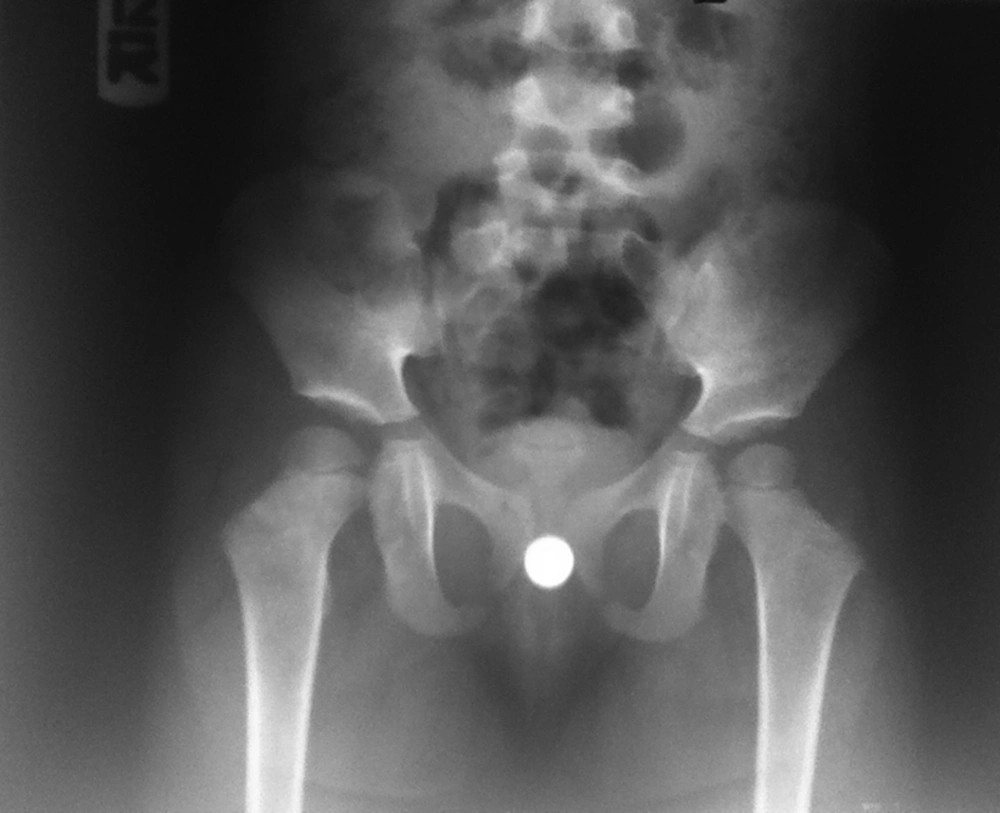

A three-year-old girl was referred to our pediatric urology clinic with chief complain of bloody discharge which increased by defecation, for more than one week. Her mother denied a history of any foreign body insertion or sexual abuse. She did not have any pruritis or voiding dysfunction. She did not take any medication. Also, her past medical and surgical histories were unremarkable. Vital signs were stable and she was afebrile at the time of admission. Chest and cardiovascular system examinations were normal. She had normal female external genitalia with no sign of erythema, skin inflammation or excoriation. Pelvic and urinary system sonography excluded any underlying pathologies such as malignancy. Pelvic X-ray revealed a round radio-opaque object in her pelvic cavity which was compatible with a button battery (Figure 1).